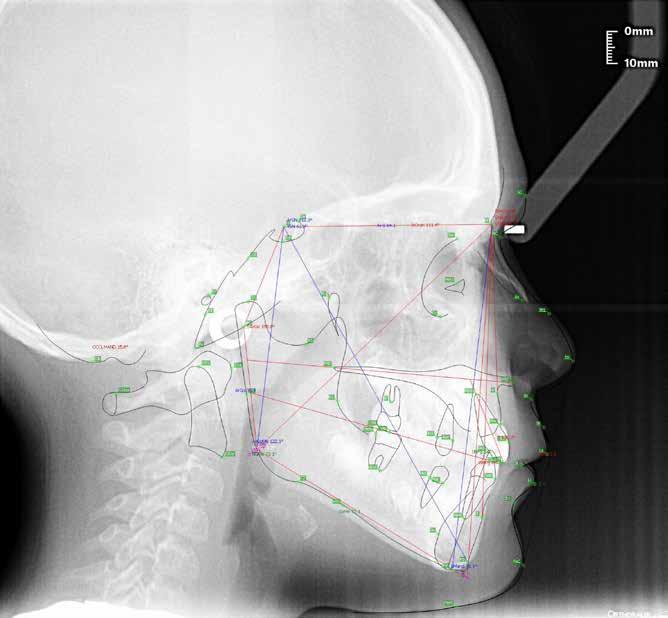

Alla risoluzione della malocclusione scheletrica e dentale si associa un netto recupero della postura con conseguente miglioramento della curva cervicale, come è possibile verificare nella teleradiografia finale.

47 46 ESTETICA FUNZIONE POSTURA Valori cefalometrici a 10 anni : ANB ANB 2.70 Posizione del Mascellare SNA 78,70 Posizione della Mandibola SNB 76.0 Angolo Articolare SArGo 142,76 Angolo Goniaco ArGoMe 125,73 Angolo incisivo inf^Corpo madibolare IiMand 92,00 Angolo incisivo Sup^Base Cranica Ant. IsCran 96,00 Angolo Interincisivo II 130,0 53 _ Esame Cefalometrico a dieci anni. 54 _ Tabella dei valori cefalometrici a dieci anni. 55 _ Ortopantomografia di controllo a dieci anni. 56 _ Teleradiografia di controllo con evidente stabilità del caso dal punto di vista scheletrico/posturale.

> La documentazione a dieci anni mostra la stabilità del caso e

come l’occlusione, elastodonticamente individuata, costituisca anche la contenzione stessa. La paziente ha smesso di

Considerazioni

indossare l’apparecchio elastodontico dopo due anni e mezzo di terapia, conservando parametri occlusali e posturali in rapporto corretto tra loro.

Nel 2019 si è provveduto all’avulsione chirurgica degli elementi dentari 18, 28, 38 e 48.